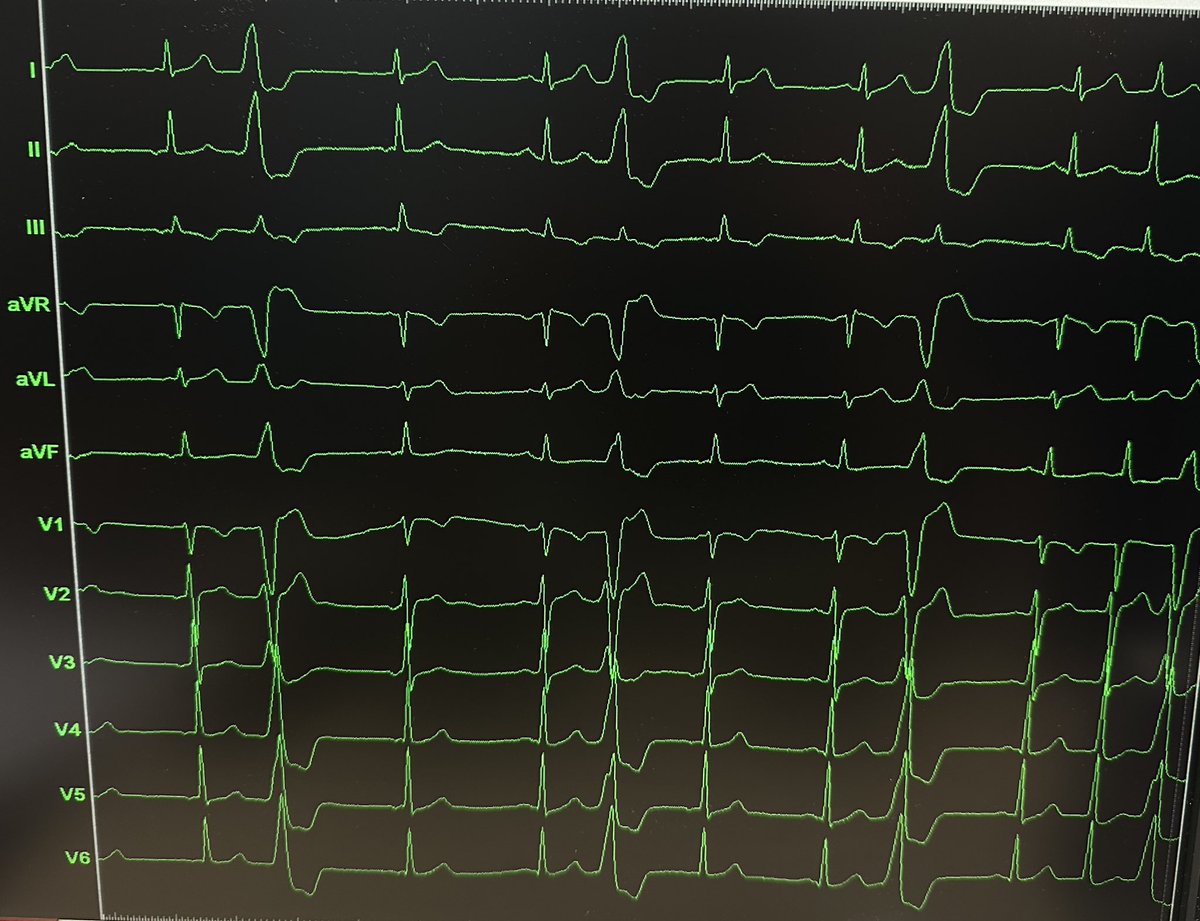

ADVANTAGE AF subanalysis: Linear bipolar PFA for CTI shows safety and efficacy comparable to RF, with greater efficiency, and supports a standardized coronary safety protocol.

Details in #JACC: jacc.org/doi/10.1016/j.…